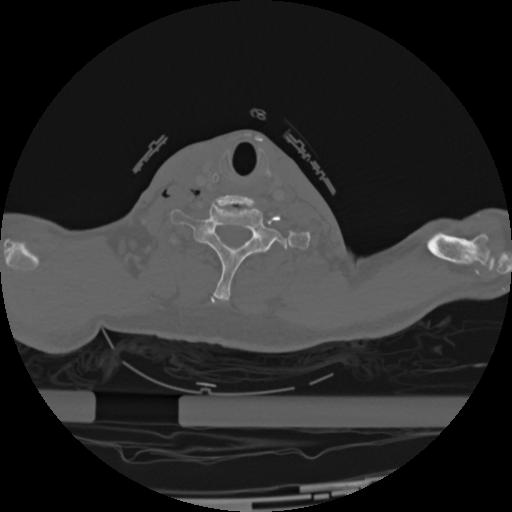

22 ANGIO,CE,Vol,0.5,ANGIO,,